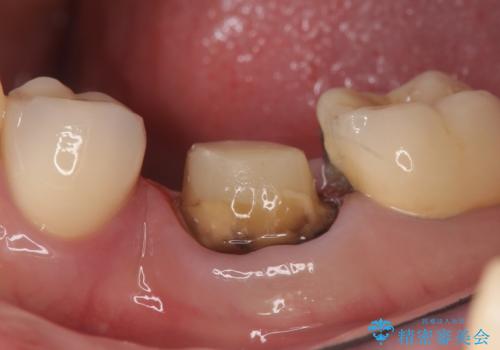

- 左下の奥歯でものを咬むと痛むので診て欲しいといらっしゃった方の症例です。

検査の結果左下6に根尖病変を認めたため、再根管治療を行いました。

その後症状の消失を確認し、オールセラミッククラウンによる補綴を行いました。